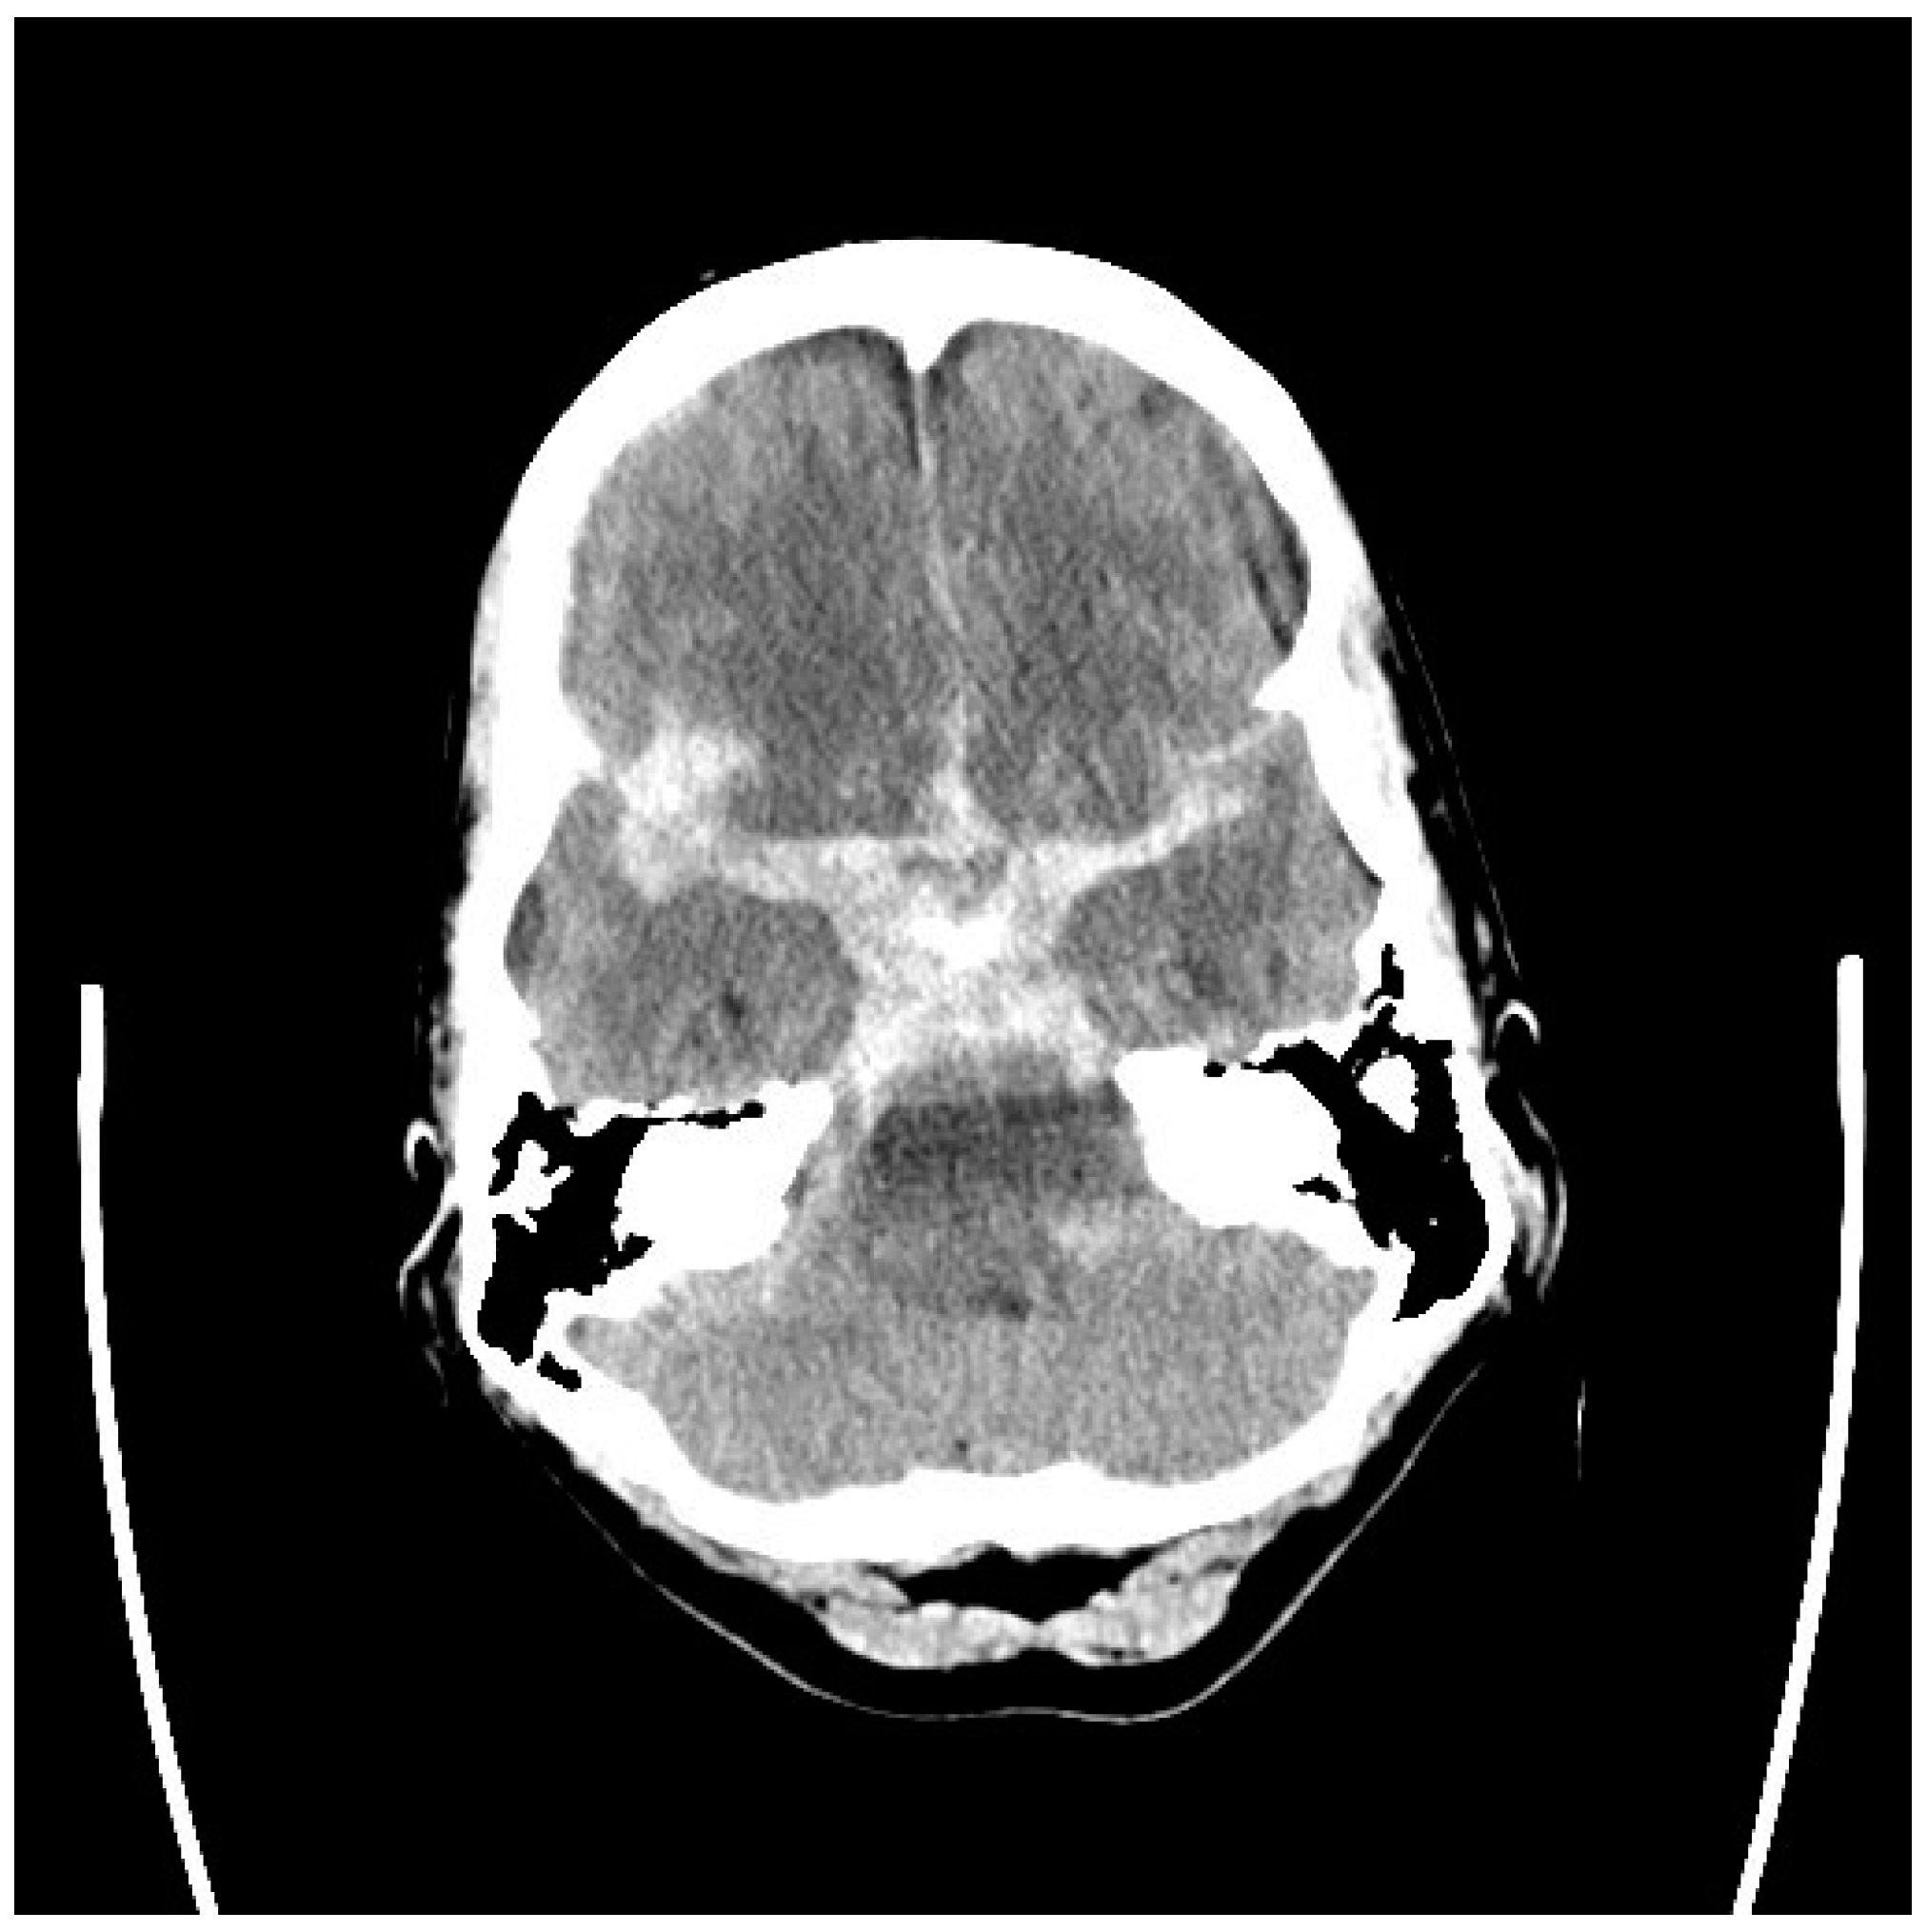

5. Diagnosis